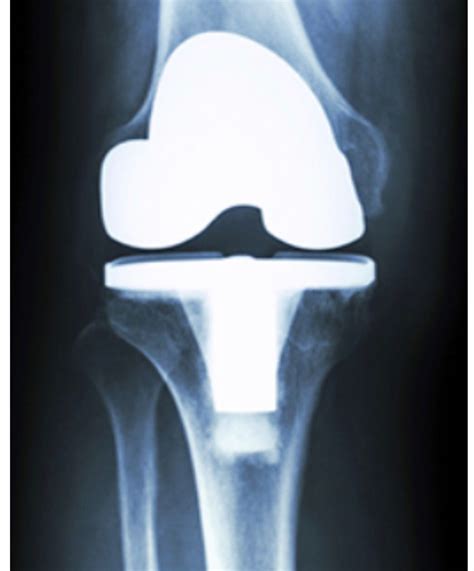

La prótesis de rodilla es un implante quirúrgico diseñado para sustituir las superficies articulares dañadas de la articulación de la rodilla, generalmente a causa de una osteoartritis avanzada, artritis reumatoide o una lesión grave. El objetivo principal es reducir el dolor causado por el desgaste del cartílago y mejorar la alineación y el funcionamiento de la articulación.

El dispositivo protésico consta generalmente de tres componentes principales:

• Componente femoral: Fabricado de aleaciones metálicas duraderas (como cobalto-cromo), reemplaza la parte inferior del fémur.

• Componente tibial: Generalmente de titanio o aleación de cobalto-cromo, reemplaza la parte superior de la tibia.

• Inserto de polietileno: Una pieza de plástico de grado médico de alta resistencia que actúa como cartílago artificial, permitiendo que el metal se deslice suavemente sobre el componente tibial.

Este reemplazo articular no solo alivia el dolor, sino que también corrige deformidades como el genu varo (rodillas en paréntesis) o el genu valgo (rodillas en forma de X), mejorando la estabilidad general del paciente.